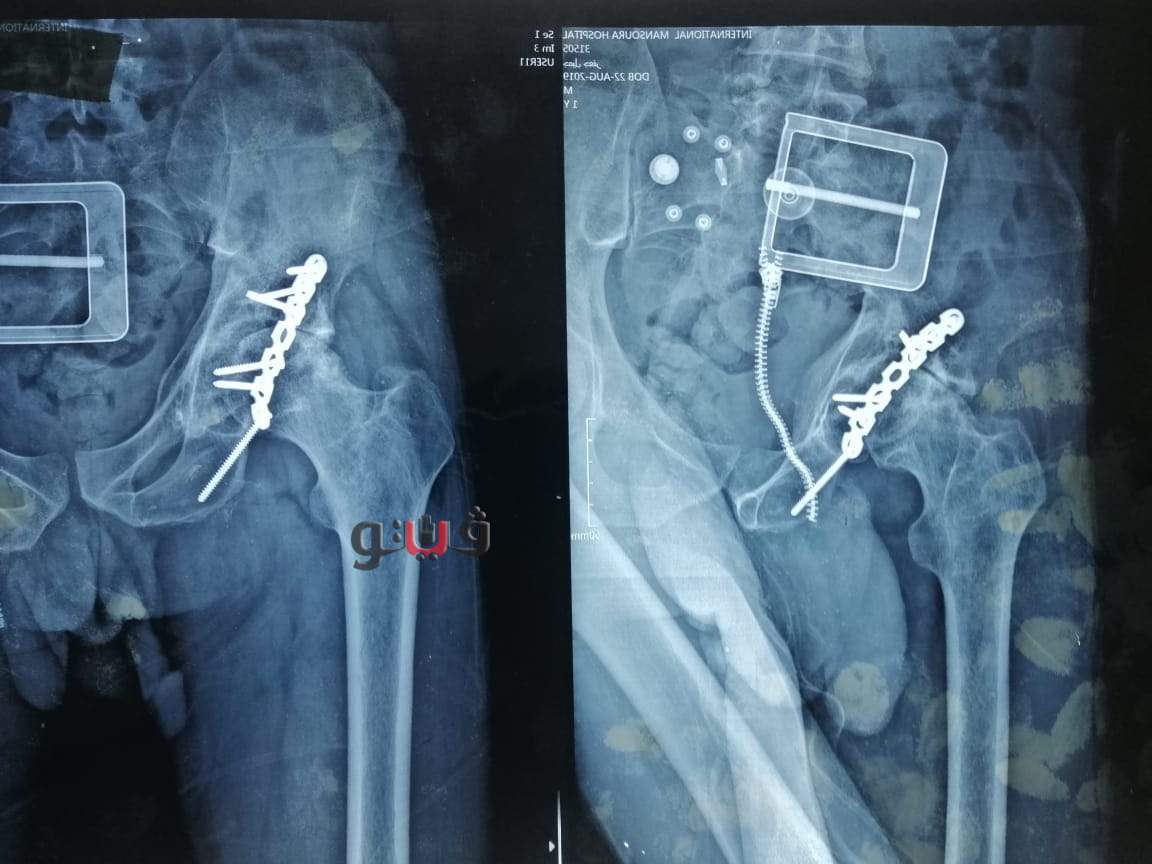

أعلن اليوم الدكتور سعد مكى وكيل وزارة الصحة بالدقهلية عن قيام فريق طبى بمستشفى المنصورة العام الجديد ، بإجراء جراحة دقيقة وحرجة لمريض يبلغ من العمر 30 عاما كان يعاني من كسر قديم في حق مفصل الحوض مثبت سابقا" بشريحة و مسامير مع وجود إصابة جزئية في العصب الوركي منذ أكثر من خمس اعوام أدت إلى خشونة حادة وتآكل في مفصل الفخذ مع وجود عرج واضح بالمشي.

وكان المريض ضمن الحالات الحرجة لقوائم الإنتظار حيث تمكن الفريق الطبى من اجراء استبدال مفصل فخذ صناعي كامل حيث استغرقت العمليه حوالي ثلاث ساعات وتعد هذه العملية من الجراحات المتقدمة ذات المهارة الخاصة.